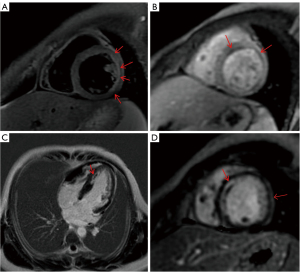

At 8 days after admission, serological examination and ECG indicated the possibility of myocardial injury or ischemia, so further cardiac magnetic resonance (CMR) plain scan + enhancement was performed, as shown in Figure 3. The main imaging findings were as follows: T2-weighted imaging (T2WI) lipid pressure sequence and T2 mapping indicated ventricular septum and anterior apex segment edema, first overperfusion of ventricular septum and anterior apex segment of myocardium in resting state, reduced subendocardial arc perfusion area, delayed scanning of ventricular septum and anterior apex segment of inferior endocardial high-line signal delayed enhancement, left heart function: left ventricular ejection fraction (LVEF) 54%, CO 4 L/min, end-diastolic volume (EDV) 112 mL, end-systolic volume (ESV) 51.8 mL. According to the characteristics of imaging findings, acute ischemic injury was confirmed.

In this case, the child, 12 years old, had no family history of heart disease. From the emergency blood examination of the patient at the initial admission, the increase in the level of hs-TnT and the obvious increase of myoglobin suggested that the chest pain of the child may be cardiogenic and the cardiac muscle of the child may be damaged. The results of ECG and CMR also confirmed the conjecture, suggesting an ischemic change in the myocardium. Subsequently, the patient underwent a series of cardiac examinations, including cardiac color ultrasound, coronary CTA, and coronary angiography, which confirmed L-ACAOS-IM. CMR, as an important non-invasive means to evaluate cardiac structure and function, has good soft tissue resolution and can well display cardiac anatomy, motor function, myocardial blood perfusion, tissue characteristics, and so on. In this case, CMR examination revealed apical ventricular septum and anterior lateral wall myocardial edema, increased T2-mapping value, decreased subendocardial perfusion, and delayed reinforcement in apical segment, indicating the possibility of acute ischemic changes in the myocardium, which also facilitated further clinical examination and laid a foundation for the later diagnosis of L-ACAOS-IM. Although heart color ultrasound is characterized by economy, simplicity, and good repeatability, it is difficult to detect coronary artery openings due to the influence of factors, such as interference of lung gas in surrounding tissues, sound transmission conditions, projection angle, and operator experience differences, which may lead to missed diagnosis. Therefore, false negative results obtained by ultrasound may need to be supplemented/supported by other examinations. As a non-invasive examination method, CCTA can clearly display the collateral circulation between the left and right coronary arteries, reliably display and classify coronary artery abnormalities, and is the preferred imaging method for detecting known or suspected coronary artery abnormalities. Finally, in the CCTA examination, it was found that the opening of the LCA was narrow and walked between the main PA, thus the diagnosis of L-ACAOS-IM was confirmed. In addition, combined with the medical history of “sudden chest pain and chest tightness after running”, it can be seen that the child had a certain exercise history before the onset of the disease. It has been pointed out in literature that exercise induces myocardial ischemia, which can lead to sudden cardiac death in severe cases (4-6). The primary pathophysiologic mechanism of myocardial ischemia in this anomaly presumably consists of compromise of the coronary arterial lumen due to the acute angle at its origin, confounded by expansion of the aorta during exercise, simulating a flaplike closure of the orifice (7-9). Since L-ACAOS-IM is associated with the risk of myocardial ischemia and sudden cardiac death, the patients should be actively treated with surgery after only 1 myocardial ischemic attack. By “unroofing” (excising the common wall between the aorta and the abnormal coronary artery) and “creating a new orifice” (modifying the opening of the abnormal coronary artery at the aorta) (8), the problem of “mechanical stenosis” caused by the LCA walking in the gap between the main PA can be effectively alleviated, so as to relieve the uncomfortable symptoms such as myocardial ischemia in patients and reduce the risk of sudden cardiac death (9).